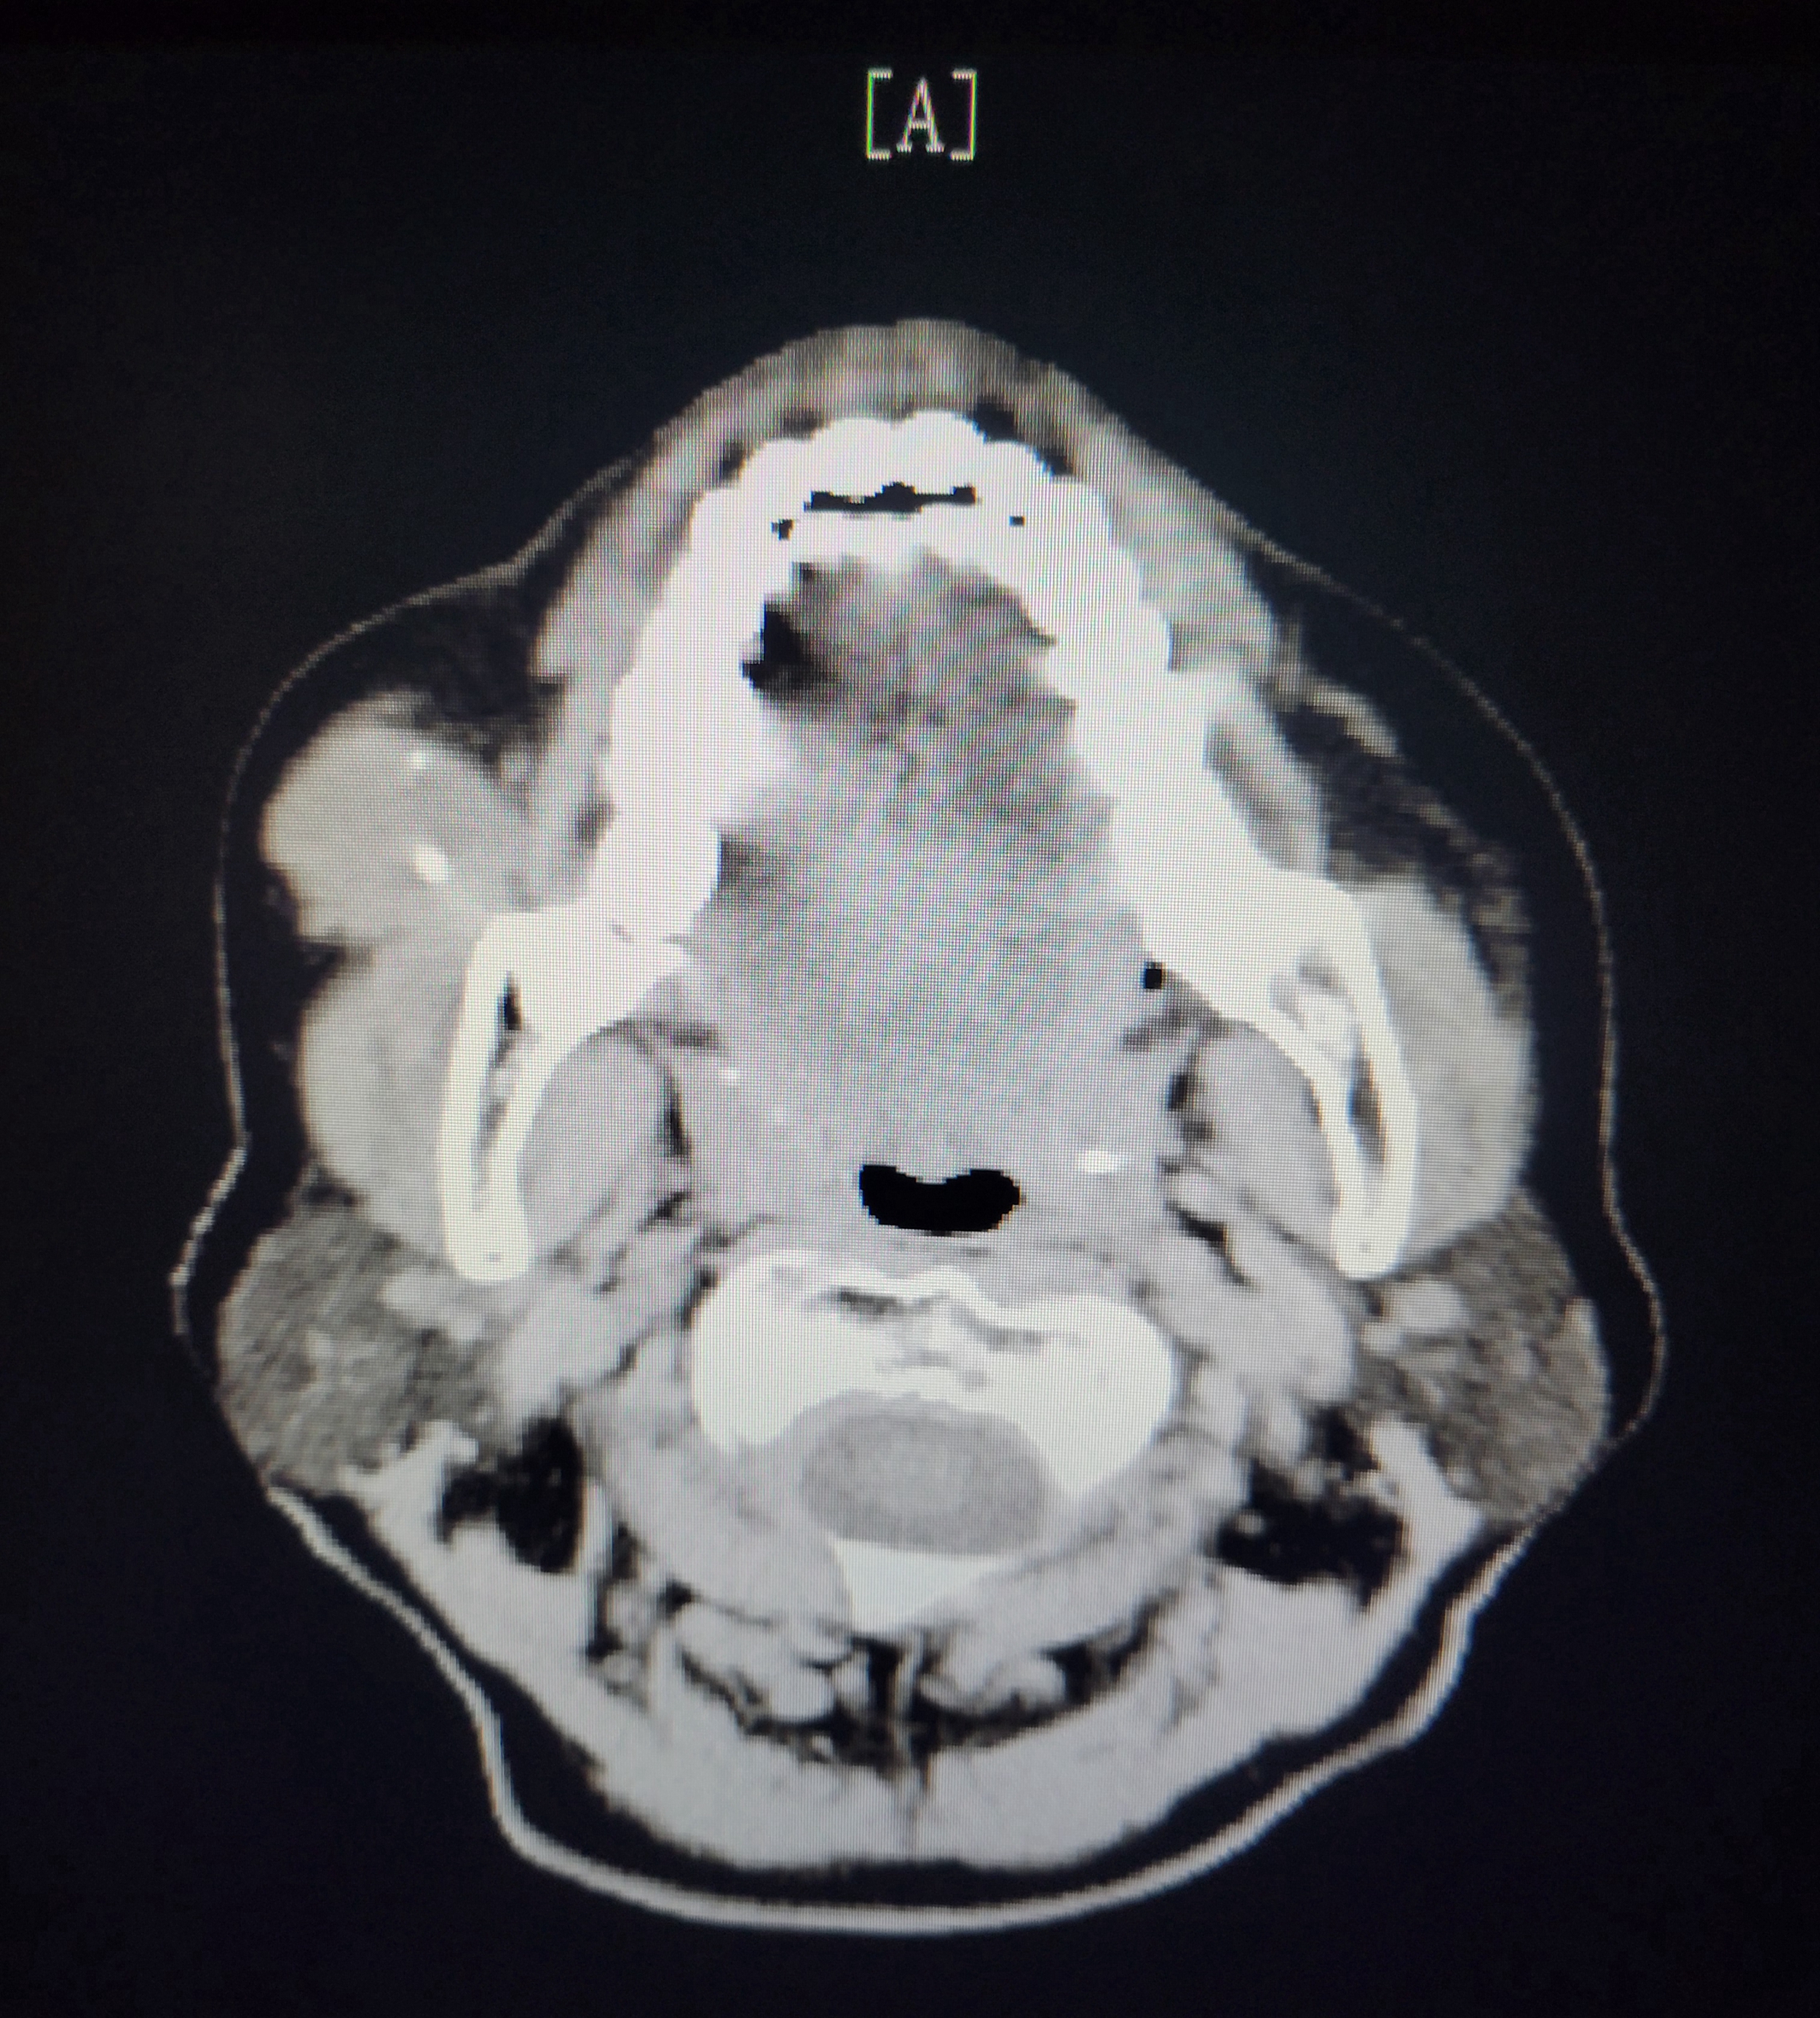

73岁的邱阿姨因“右颊部无痛性肿物半年”来到我院口腔科就诊,弋矶山医院陈亮主任和我院口腔科喻启友主任询问病史,通过查体及影像检查发现该患者:右侧咬肌前方软组织团块伴钙化灶,临床考虑为:脉管畸形(静脉畸形),其内钙化灶为静脉石可能,口腔科遂以“右颊部脉管畸形”收住院行手术摘除。考虑到肿物较大(直径约3.5cm,质软,按压时肿物消失,完整摘除难度大),手术采用口外切口,自耳屏前至下颌下做切口、翻瓣。

“静脉畸形,属于脉管畸形的一种,过去常被称为海绵状血管瘤,由大小不等的扩张静脉构成,犹如海绵状结构,窦腔内血液凝固后形成血栓,可钙化为静脉石。”陈亮主任介绍说,“静脉畸形好发于颊面部,位置较深的话,皮肤或黏膜颜色可正常,扪之柔软,边界不清,体位移动试验阳性,早期可无自觉症状,随着病变不断发展,可伴有吞咽、语言及呼吸功能障碍,并有出血的危险。静脉畸形可采用激光治疗、硬化治疗和手术治疗,激光、硬化需要多次治疗且易复发,本病例CT显示病变范围界限尚清楚,窦腔内存在静脉石,手术基本上能一次性根治,手术的难度在于术中注意保护面神经及减少出血。”